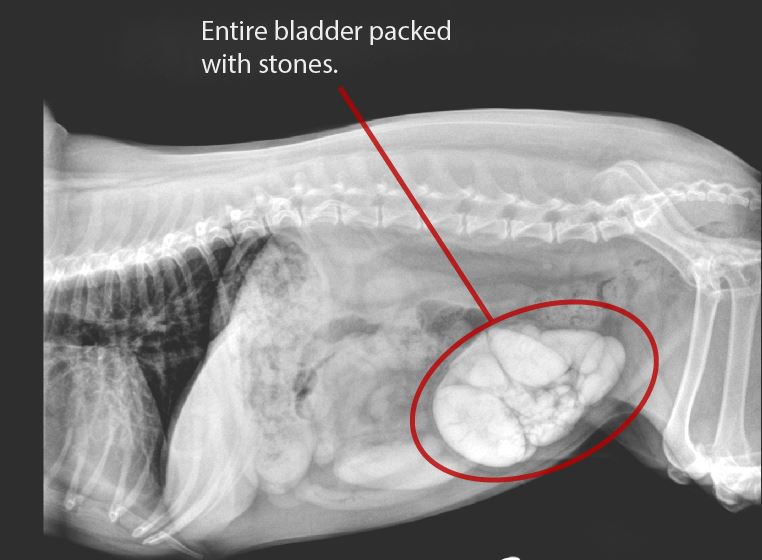

Abby's Story

Our girl Abby wasn't going to make it. She had 18 bladder stones—one almost as big as a fist. U.S. surgery was way too expensive, but here in Rocky Point we had it done for half the cost, and gained five precious years with her.